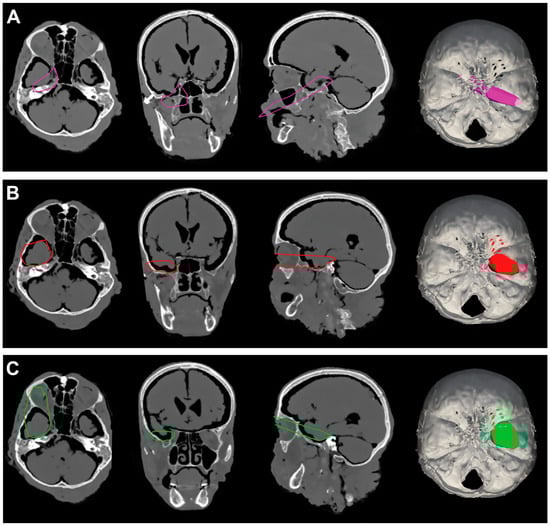

Figure 7.

(A). Exemplificative screenshot from Approach Viewer of the RSA with 10 mm of retraction. (B). Exemplificative screenshot from Approach Viewer of the RSA with 10 mm of retraction. (C). Exemplificative screenshot from Approach Viewer of the RSAS with 10 mm of retraction. (D). Exemplificative screenshot from Approach Viewer of the RSAS with 15 mm of retraction.